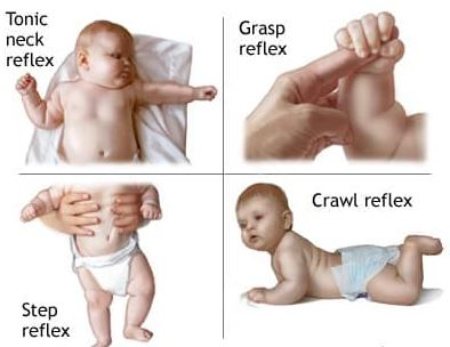

انواع بازتابها

نوزادان دارای چندین نوع بازتاب هستند که به طور عمده شامل موارد زیر میشوند:

بازتاب ساکن

نوزادان با فشار بر روی پاهای خود، به طور خودکار به سمت بالا حرکت میکنند. این بازتاب نشاندهنده سلامت عصبی نوزاد است.

بازتاب گرفتن

نوزادان به طور طبیعی به فشار بر روی دست یا پاهای خود پاسخ میدهند و آنها را به سمت خود میکشند.

3. چه نوع بازتابهایی در نوزادان وجود دارد؟

برخی از انواع بازتابهای نوزادان شامل بازتاب مورو، بازتاب جستوجو، بازتاب گرفتن، و بازتاب ساکن هستند. هر یک از این بازتابها نشاندهنده وضعیت خاصی در سیستم عصبی نوزاد است.